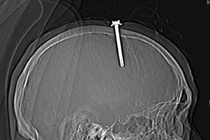

Dị vật xuyên màng não là cấp cứu ngoại khoa nghiêm trọng, tùy theo vị trí tổn thương của dị vật mà có thể dẫn đến các biến chứng nguy hiểm như: yếu liệt chi, rối loạn chức năng sống, áp xe não, thậm chí tử vong.